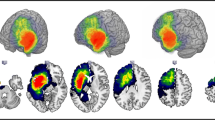

Fibre tractography

Group commonality maps of structural connections seeding from the bilateral posterior inferior temporal gyrus (auditory naming; Fig. 2) and left fusiform gyrus (picture naming; Fig. 2) showed that connections extended anteriorly to the temporal lobes including the temporal poles, and posteriorly to middle and inferior occipital gyri and precuneus, as well as to frontal and prefrontal regions. The distribution of tract volumes and laterality indices is displayed in online resource 5.

A Seed regions for tractography derived from fMRI activation maxima during auditory naming (left three columns) and picture naming (right three columns). B Group commonality maps (at a probability threshold of 0.01) of tracts seeding from the fMRI-guided seeds in the left posterobasal temporal lobe for left TLE and right TLE. Images show left, right, and top view surface renderings with embedded spatial distribution of tracts. The colour scale indicates the degree of overlap of tracts among subjects, expressed as a commonality value. A commonality value of 1 indicates an overlap of 100% of subjects having connections in the respective voxel, and a value of 0 indicates that no subject has connections. Similar connection patterns were observed for left TLE and right TLE, with consistent connections from the posterobasal temporal lobes to bilateral anterior temporal lobes, angular gyrus and occipital cortex, frontal and prefrontal regions